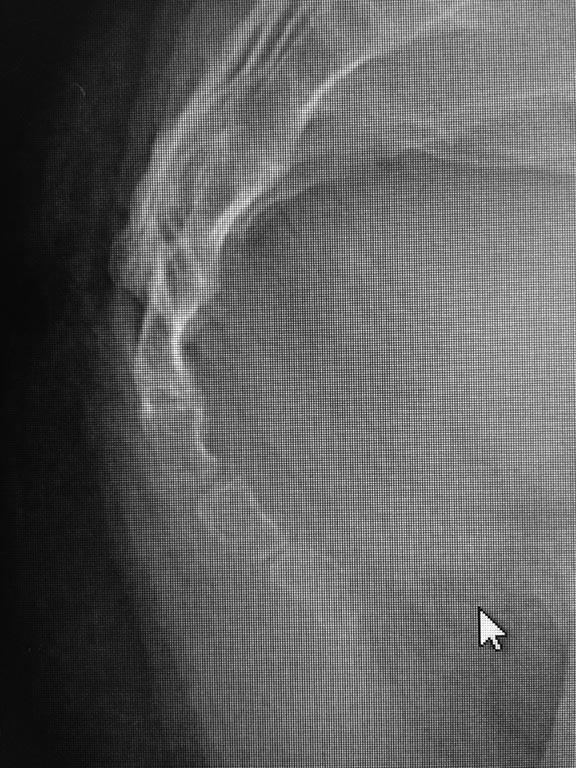

Добрый день! Три дня назад я упала, сегодня сделали снимки копчика в районной поликлинике, один врач думал перелом, другой подвывих.

Никаких проблем на снимке не видно. Либо это сильный ушиб, либо проблема в другом месте.